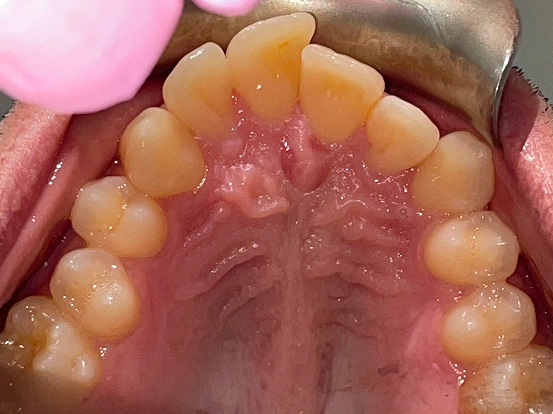

Invisalign CK

This Invisalign case shows how clear aligners can completely transform a smile without the need for metal braces. Over the course of treatment, CK achieved a beautifully aligned smile with improved symmetry and confidence. The results highlight how Invisalign offers both comfort and precision for a stunning new look.